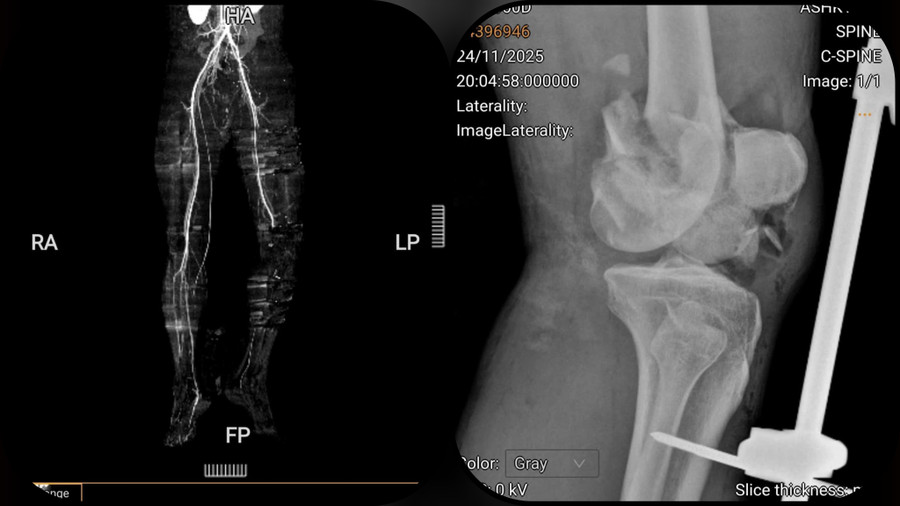

Phim CT mạch máu tổn thương hoàn toàn động mạch khoeo chân trái và Xquang gãy liên lồi cầu đùi trái di lệch nhiều.

Ca phẫu thuật là sự phối hợp giữa chuyên khoa Chấn thương chỉnh hình và Mạch máu. BS.CKII Nguyễn Thành Hưng, khoa Lồng ngực - Mạch máu, xử lý vùng hố khoeo với cấu trúc giải phẫu phức tạp. Do động mạch khoeo đã đứt rời và mất một đoạn dài hơn 2cm, các bác sĩ phải dùng kỹ thuật vi phẫu, lấy tĩnh mạch hiển tự thân ở chân lành làm "cầu nối" để đưa dòng máu ấm về nuôi chân bị thương.